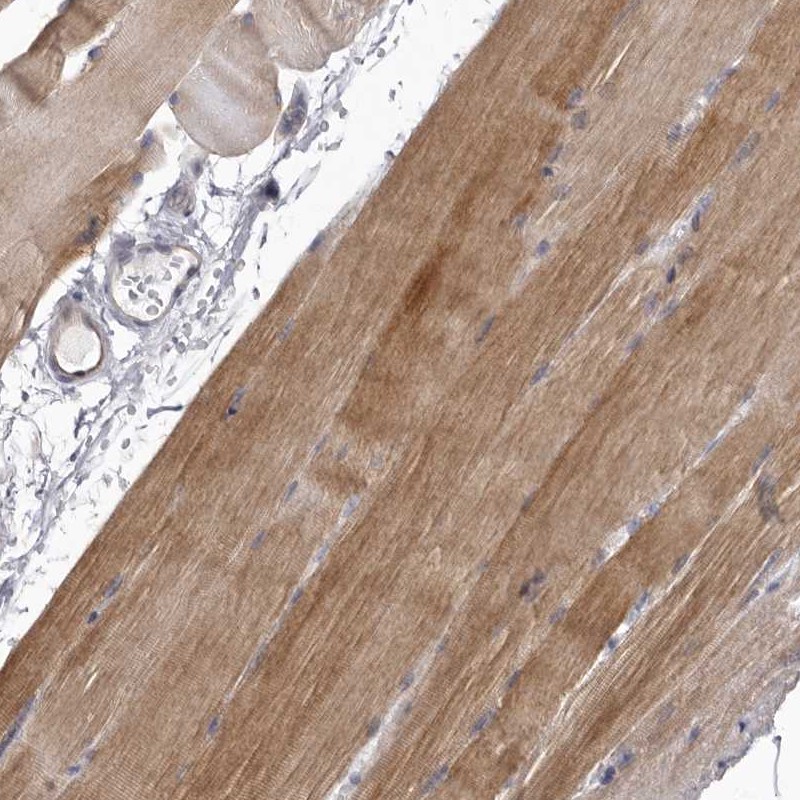

Immunohistochemical staining of human skeletal muscle shows moderate cytoplasmic positivity in myocytes.